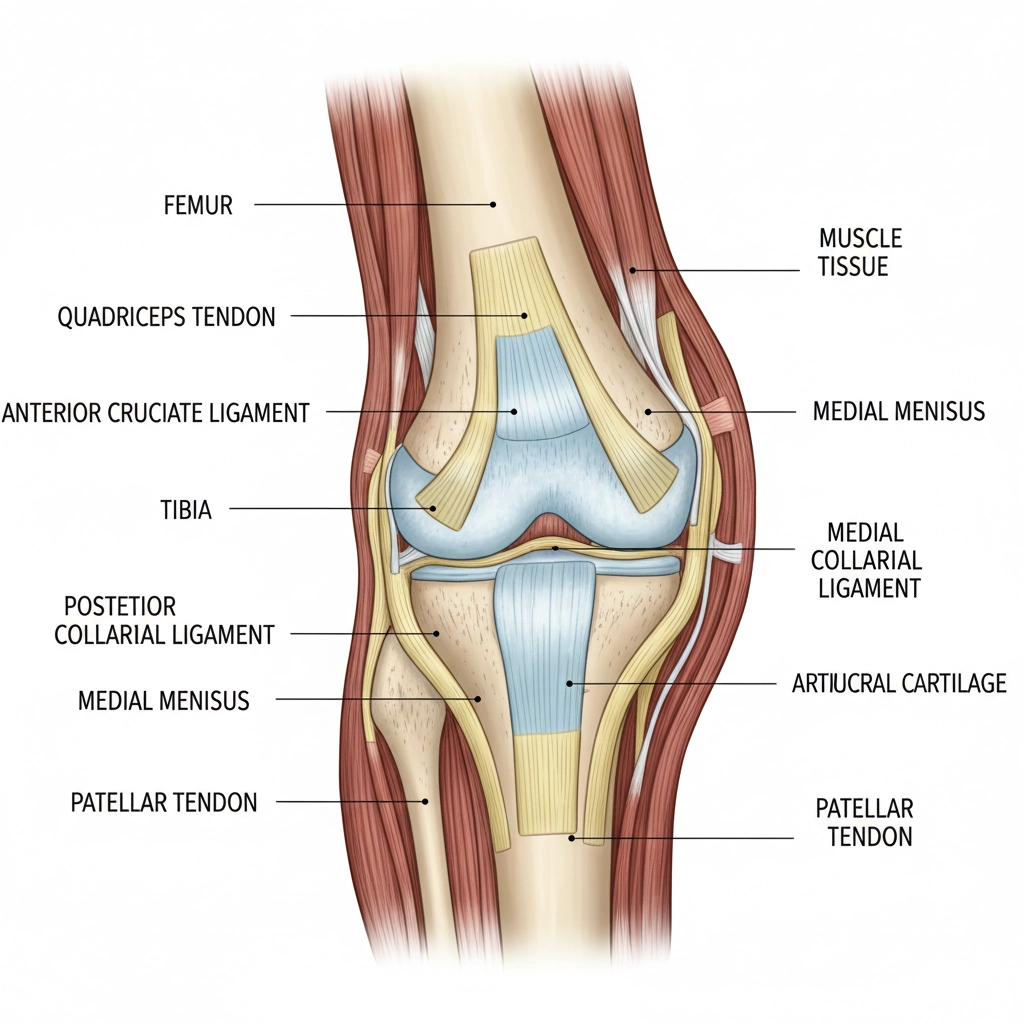

Professional Athletic Recovery

Elite athletes trust Clayer because consistency equals results. When recovering from training or injury, you need reliable therapeutic benefits. DIY mixes can't provide this level of predictable healing support.

Champions don't gamble with recovery, they use proven solutions.

Professional therapists and sports medicine practitioners recommend Clayer because it delivers the same therapeutic benefits every single time. No guesswork, no inconsistent batches: just reliable healing support.

Your body deserves professional-grade care.